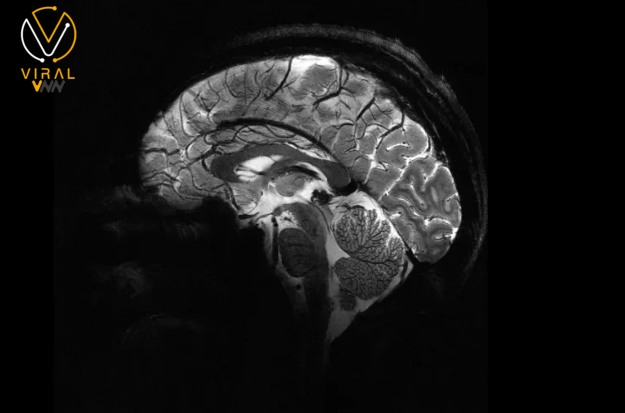

تقنية تصوير الدماغ بدقة فائقة باستخدام أحدث أجهزة الرنين المغناطيسي حيث أصدرت هيئة الطاقة الذرية في فرنسا صورة هي الأدق على الإطلاق لدماغ إنسان بعد الحصول على الموافقة النهائية لاستخدام أحدث جهاز تصوير بالرنين المغناطيسي.

يبلغ شدة المجال المغناطيسي الذي يولده الجهاز حوالي 11.7 تسلا،

مما يمكّنه من إجراء عمليات المسح بدقة أكبر بعشر مرات مقارنة بأجهزة التصوير بالرنين المغناطيسي التقليدية في المستشفيات، التي تكون قوتها عادة حوالي 3 تسلا.

من خلال مقارنة الصور الملتقطة بواسطة الجهاز الجديد مع صور من أجهزة التصوير التقليدية، يقول فيغنود إنهم نجحوا بفضل استخدام الماسح الضوئي القوي في رؤية الأوعية الصغيرة التي تغذي القشرة الدماغية،

وتمكنوا من ملاحظة تفاصيل المخيخ التي لم يسبق الكشف عنها قبل ظهور الصور الجديدة.